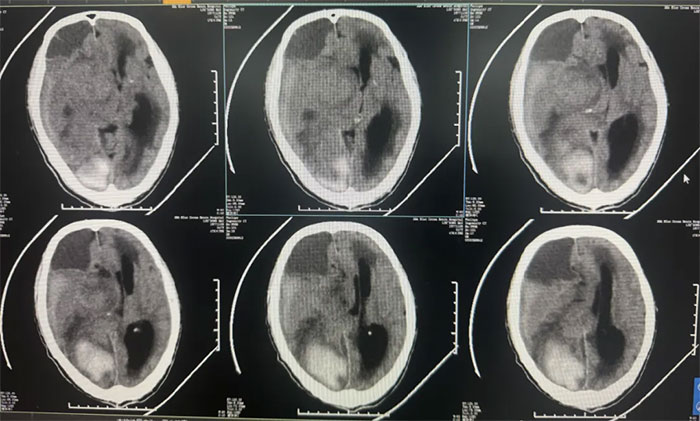

右頂枕葉出血,右側額顳頂部亞急性硬膜下血腫,大腦鐮下疝形成。

14天前突發(fā)神志不清,外院查頭顱CT提示“腦出血,腦疝形成”。未手術,予脫水降顱壓等保守治療。